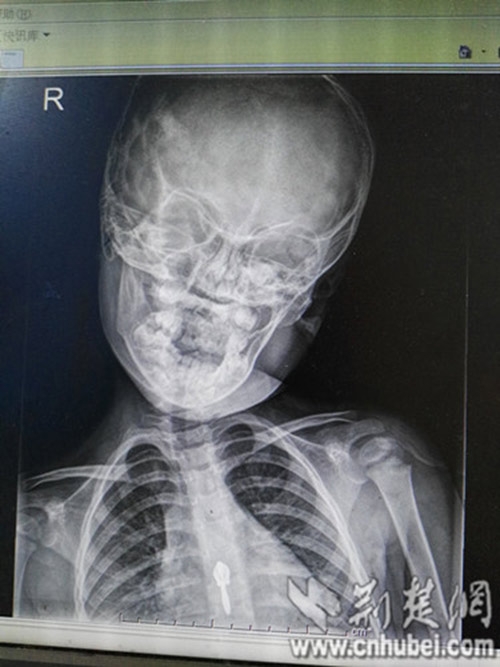

Theo một bài viết được chia sẻ "chóng mặt" trên trang Sports Network (Trung Quốc), sau khoảng 1 năm đều đặn sử dụng điện thoại và máy tính bảng, một bé gái 3 tuổi đã phải nhập viện khẩn cấp và trở thành bệnh nhân "nhí" tại khoa Phục hồi chức năng để điều trị bệnh lệch cổ, thoái hóa đốt sống cổ.

Theo bác sĩ Hồ Tiểu Quân, giám đốc bệnh viện Phổ Nhân, trẻ em trong một thời gian dài ngồi yên một chỗ để chơi iPad, điện thoại di động sẽ gây ra đau cơ cổ, căng thẳng, co thắt dây chằng, nếu không can thiệp, nguy cơ trong tương lai sẽ bị thoát vị đĩa đệm cổ và các bệnh khác.

Hiện tượng này cũng xảy ra phổ biến và lứa tuổi ngày càng nhỏ. Không những thế, thoái hóa đốt sống cổ ở trẻ em còn gây nguy hiểm lớn hơn rất nhiều so với người lớn, và thiệt hại đối với cuộc sống của trẻ là không hề nhỏ.

![]() |

Ngoài ra, xương của trẻ em đang trong giai đoạn phát triển, căn bệnh này có thể ảnh hưởng đến kích thước của đốt sống cổ, phát triển dị dạng, trường hợp nghiêm trọng thậm chí có thể ảnh hưởng đến ngực, thắt lưng và các phần xương khác, thậm chí làm hạn chế phát triển chiều cao.

"Nhiều bậc cha mẹ có thể nghĩ rằng, cho con một chiếc điện thoại di động hoặc máy tính bảng thì bé sẽ ngồi yên tĩnh, nhưng không chú ý đến tư thế của cổ, đã dẫn đến sự xuất hiện của bệnh.

Khi trẻ em chơi trò chơi, chúng sẽ ngồi yên "bất động" và giữ tư thế đó trong một thời gian dài. Lâu và thường xuyên như vậy, cổ sẽ cúi gập xuống gây võng xương.

Cách ngồi như vậy có tác hại tĩnh, không nhìn thấy ngay lập tức, trẻ sẽ cảm thấy đau từ từ mỗi hôm một ít, cộng với ban đêm ngủ trong phòng điều hòa lạnh, đặc biệt dễ bị tổn thương dẫn đến cứng cổ.